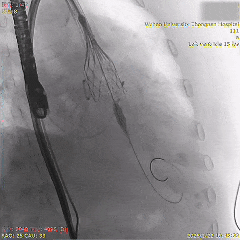

为降低起搏器风险,追求更完美精准植入,选择回收重新定位释放

第二次瓣膜稳定释放

全展开位评估:左右重合体位造影可见无冠窦侧深度约为瓣下1mm

全展开位评估:左冠切线位造影可见左窦侧深度约为瓣下5mm

充分评估后选择脱钩,瓣膜稳定释放,无二次位移